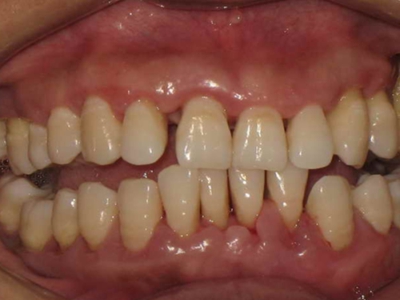

牙龈炎是发生于牙龈组织的炎症,患者可出现牙龈出血伴肿胀、发红、正常形态改变和偶尔不适等症状。本病主要由口腔卫生状况差导致,包括口腔不洁、牙菌斑等,诊断依据临床检查,治疗包括专业牙齿清洁和加强家庭口腔卫生。

牙龈炎可先引起牙齿与牙龈之间的沟(龈沟)加深,然后牙龈充血,炎症围绕一个或多个牙齿,伴牙龈乳头肿胀和易出血。一般无痛,可自行消退,也可维持轻度炎症数年。

牙龈炎常见的病因是口腔卫生差,不良的口腔卫生使牙菌斑沉积于牙齿与牙龈之间,造成龈沟加深,另外牙结石、不良修复体等也可造成牙龈炎的发生。